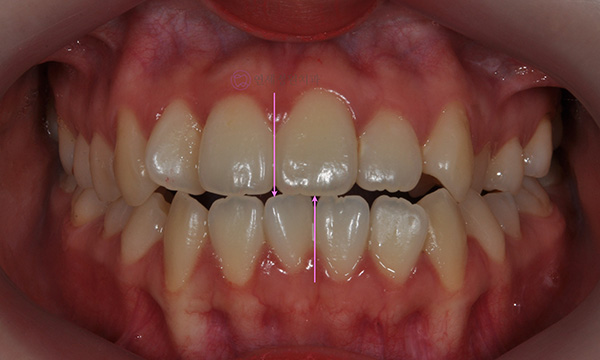

위 환자분은 치아 중심선이 맞지 않는다는 주소로 치과에 내원하셨습니다. 미소시 사진을 보면 위 치아도 오른쪽(사진 상 왼쪽)으로 틀어져 있고, 아래 치아도 왼쪽(사진 상 오른쪽)으로 틀어져 있었습니다. 그리고 양쪽 입꼬리 근육의 활성도도 차이가 있어서, 웃었을 때 왼쪽 입꼬리가 오른쪽보다 덜 올라가서 비대칭이 더 강조되어 보였습니다.

치아 중심선의 차이를 개선하고, 얼굴의 중심과 치열의 중심을 맞춰주기 위하여 오른쪽 아래 작은 어금니를 하나만 발치하여 그 공간으로 아래 치열을 오른쪽으로 돌려주고, 위 치열은 전체적으로 왼쪽으로 치열을 이동시켜서 중심선을 맞추어 주었습니다.

위 아래 치아의 중심선이 일치하고 좌우 어금니의 교합도 잘 맞춰졌습니다. 좌우 입꼬리 올림근 활성도의 차이는 남아있음에도 얼굴의 중심과 위 아래 치아의 중심이 일치하여 미소시에도 교정 전보다 훨씬 자연스러운 미소를 짓게 되었습니다.